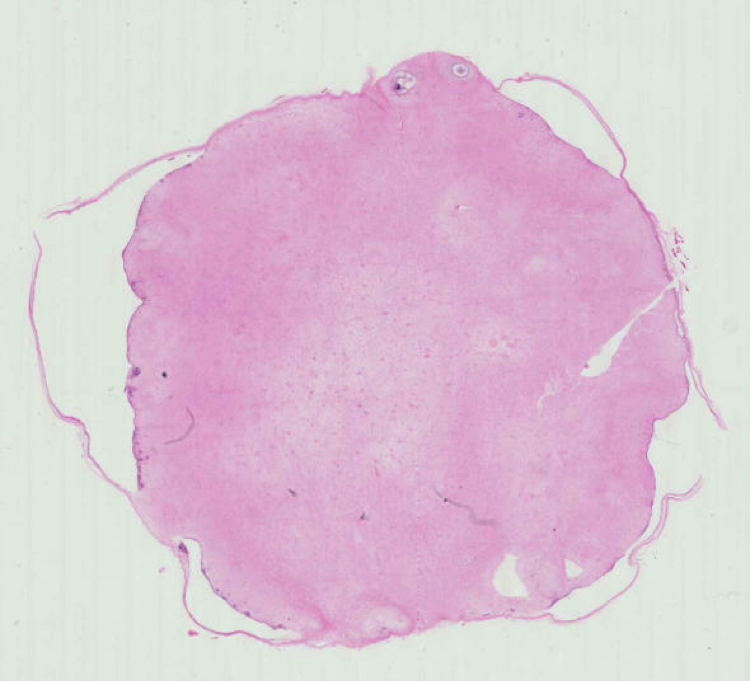

Las investigaciones del Dr, Mosqueda arrojan que los quistes y tumores odontogénicos representan un grupo heterogéneo de entidades que incluye tanto lesiones hamartomatosas (crecimientos benignos [no cancerosos] compuestos por una mezcla de células y tejidos en estructura y ubicación anatómica normales, pero en cantidad anormalmente mayor), como neoplasias benignas y malignas con grados variables de agresividad. Estas lesiones en su conjunto representan la principal causa de destrucción del esqueleto facial.

Por tener un origen común, a menudo su morfología produce dificultades diagnósticas que inciden en un manejo inadecuado, por lo que es necesario conocer con mayor profundidad su origen y mecanismos implicados en su desarrollo y expresión clínico-patológica como fundamento para su diagnóstico preciso y para definir la terapéutica más adecuada en cada caso.